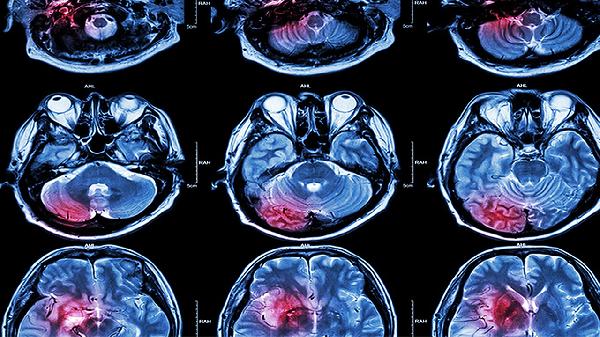

中风患者除规范用药外,需严格控制血压、血糖及血脂水平,低盐低脂饮食并适量补充优质蛋白。康复期应在专业指导下进行肢体功能训练和语言康复,避免吸烟酗酒,定期复查头颅影像学及血液流变学指标。突发头痛呕吐或症状加重时须立即就医。